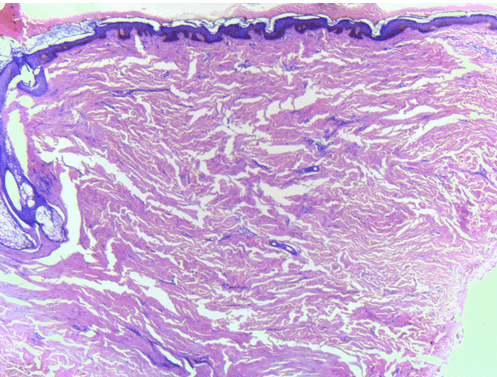

An 18-year-old female with history of delayed milestones, low IQ, and typical Mongolian facies (Figure 1) (typical slant of forehead, and macroglossia) presented to our outpatient department with abrupt onset of asymptomatic skin colored nodules within a period of one month on upper back. The patient did not report any previous history of chicken pox/ trauma at the involved site. Her family history was unremarkable. A review of the various organ systems (cardiovascular, respiratory, gastrointestinal tract, central nervous system) was within normal limits. Examination revealed multiple, discrete, firm, non-tender, skin colored nodules measuring 0.5 to 2 cm in diameter with no scaling or exudation on the surface. The lesions were present predominantly on upper 2/3 of back and on thorough cutaneous examination similar lesions were present on the mons pubis, which as per patient developed 6 months back (Figure 2) and (Figure 3). We kept the differentials of eruptive xanthoma, steatocystoma multiplex and eruptive collagenoma. There was no evidence of hypopigmented macules on wood's lamp examination or skin lesions suggestive of tuberous sclerosis. There was no significant past medical or surgical history. The hematological and biochemical investigations including complete blood count, renal, liver function tests, urine analysis, lipid profile, electrocardiogram, abdominal ultrasound and chest roentgenogram were within normal limits. Skeletal survey did not demonstrate any evidence of osteopoikilosis. A skin biopsy obtained from the lesion on upper back and mons pubis showed focal acanthotic epidermis and significantly increased density of collagen bundles in the deep reticular dermis (Figure 4). Masson's trichrome stain confirmed the presence of dense collagen bundles with decreased elastic fibers (Figure 5). Thus a diagnosis of sporadic eruptive collagenoma with Down syndrome was made.

Figure 4: Focal acanthotic epidermis with significantly increased collagen bundles in dermis.